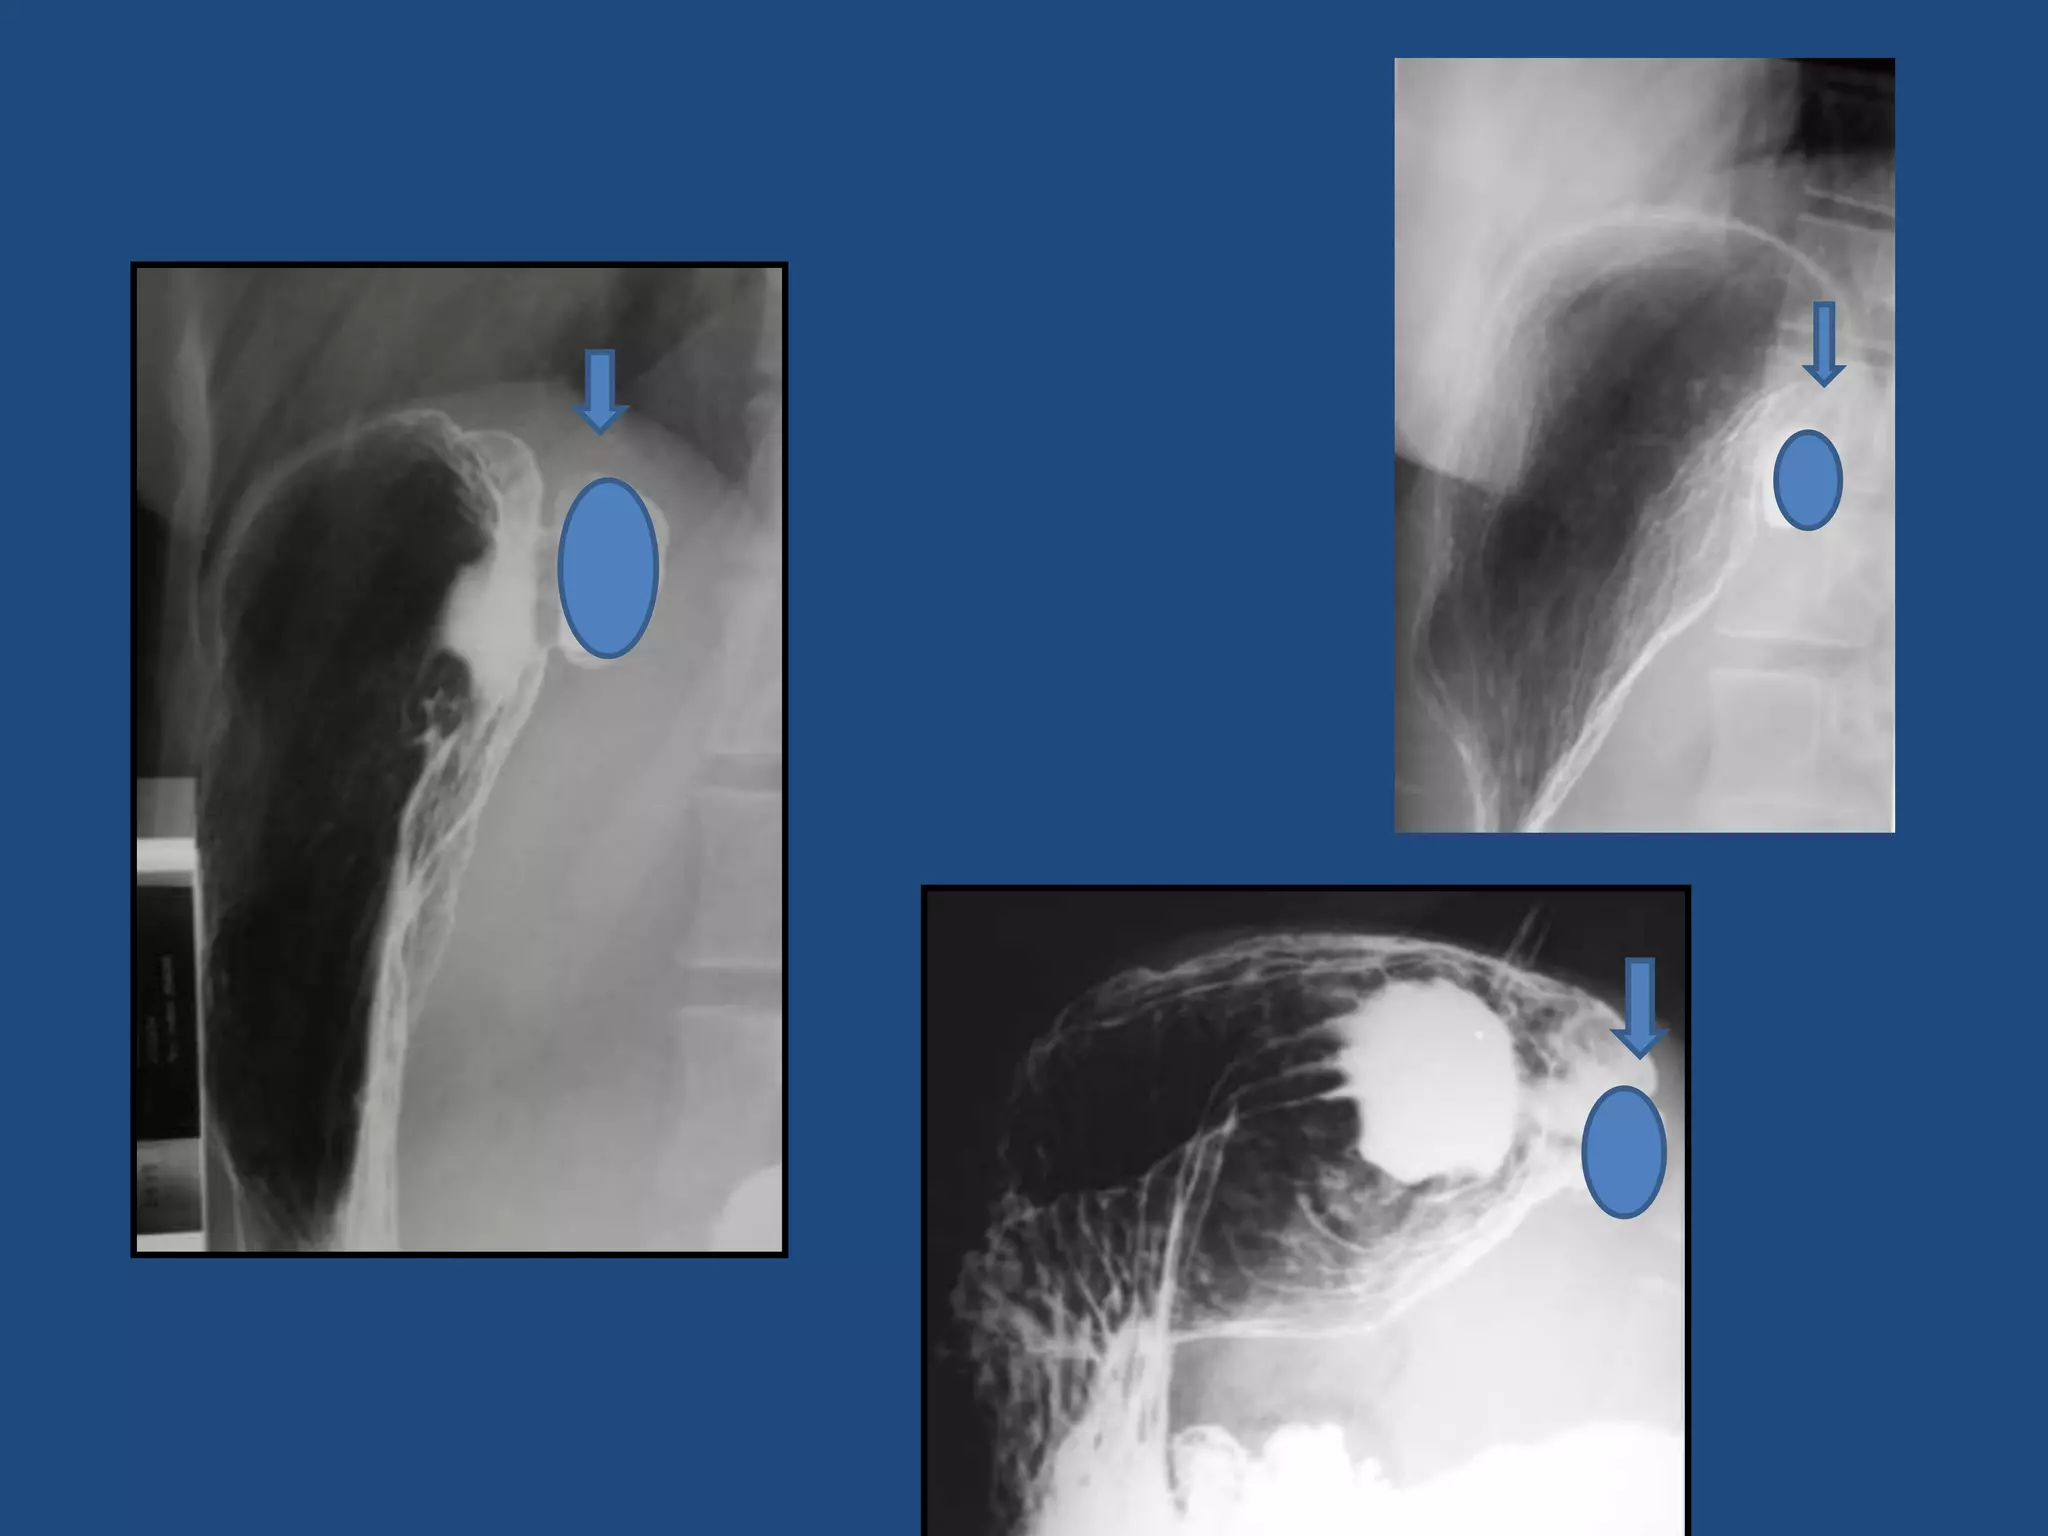

ESTOMAGO: ULCERA GASTRODUODENAL

RADIOLOGÍA CONTRASTADA

VISUALIZACION

DEL NICHO ULCEROSO

(Depresión con relleno de bario)

ESTOMAGO: ÚLCERA GASTRODUODENAL

Nicho

ulceroso

+

Pliegues

convergentes

Nicho ulceroso en

bulbo duodenal

Nichos ulcerosos con pliegues que convergen